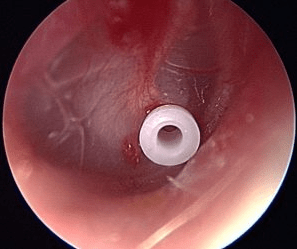

- Minor procedures: grommets or balloon dilation